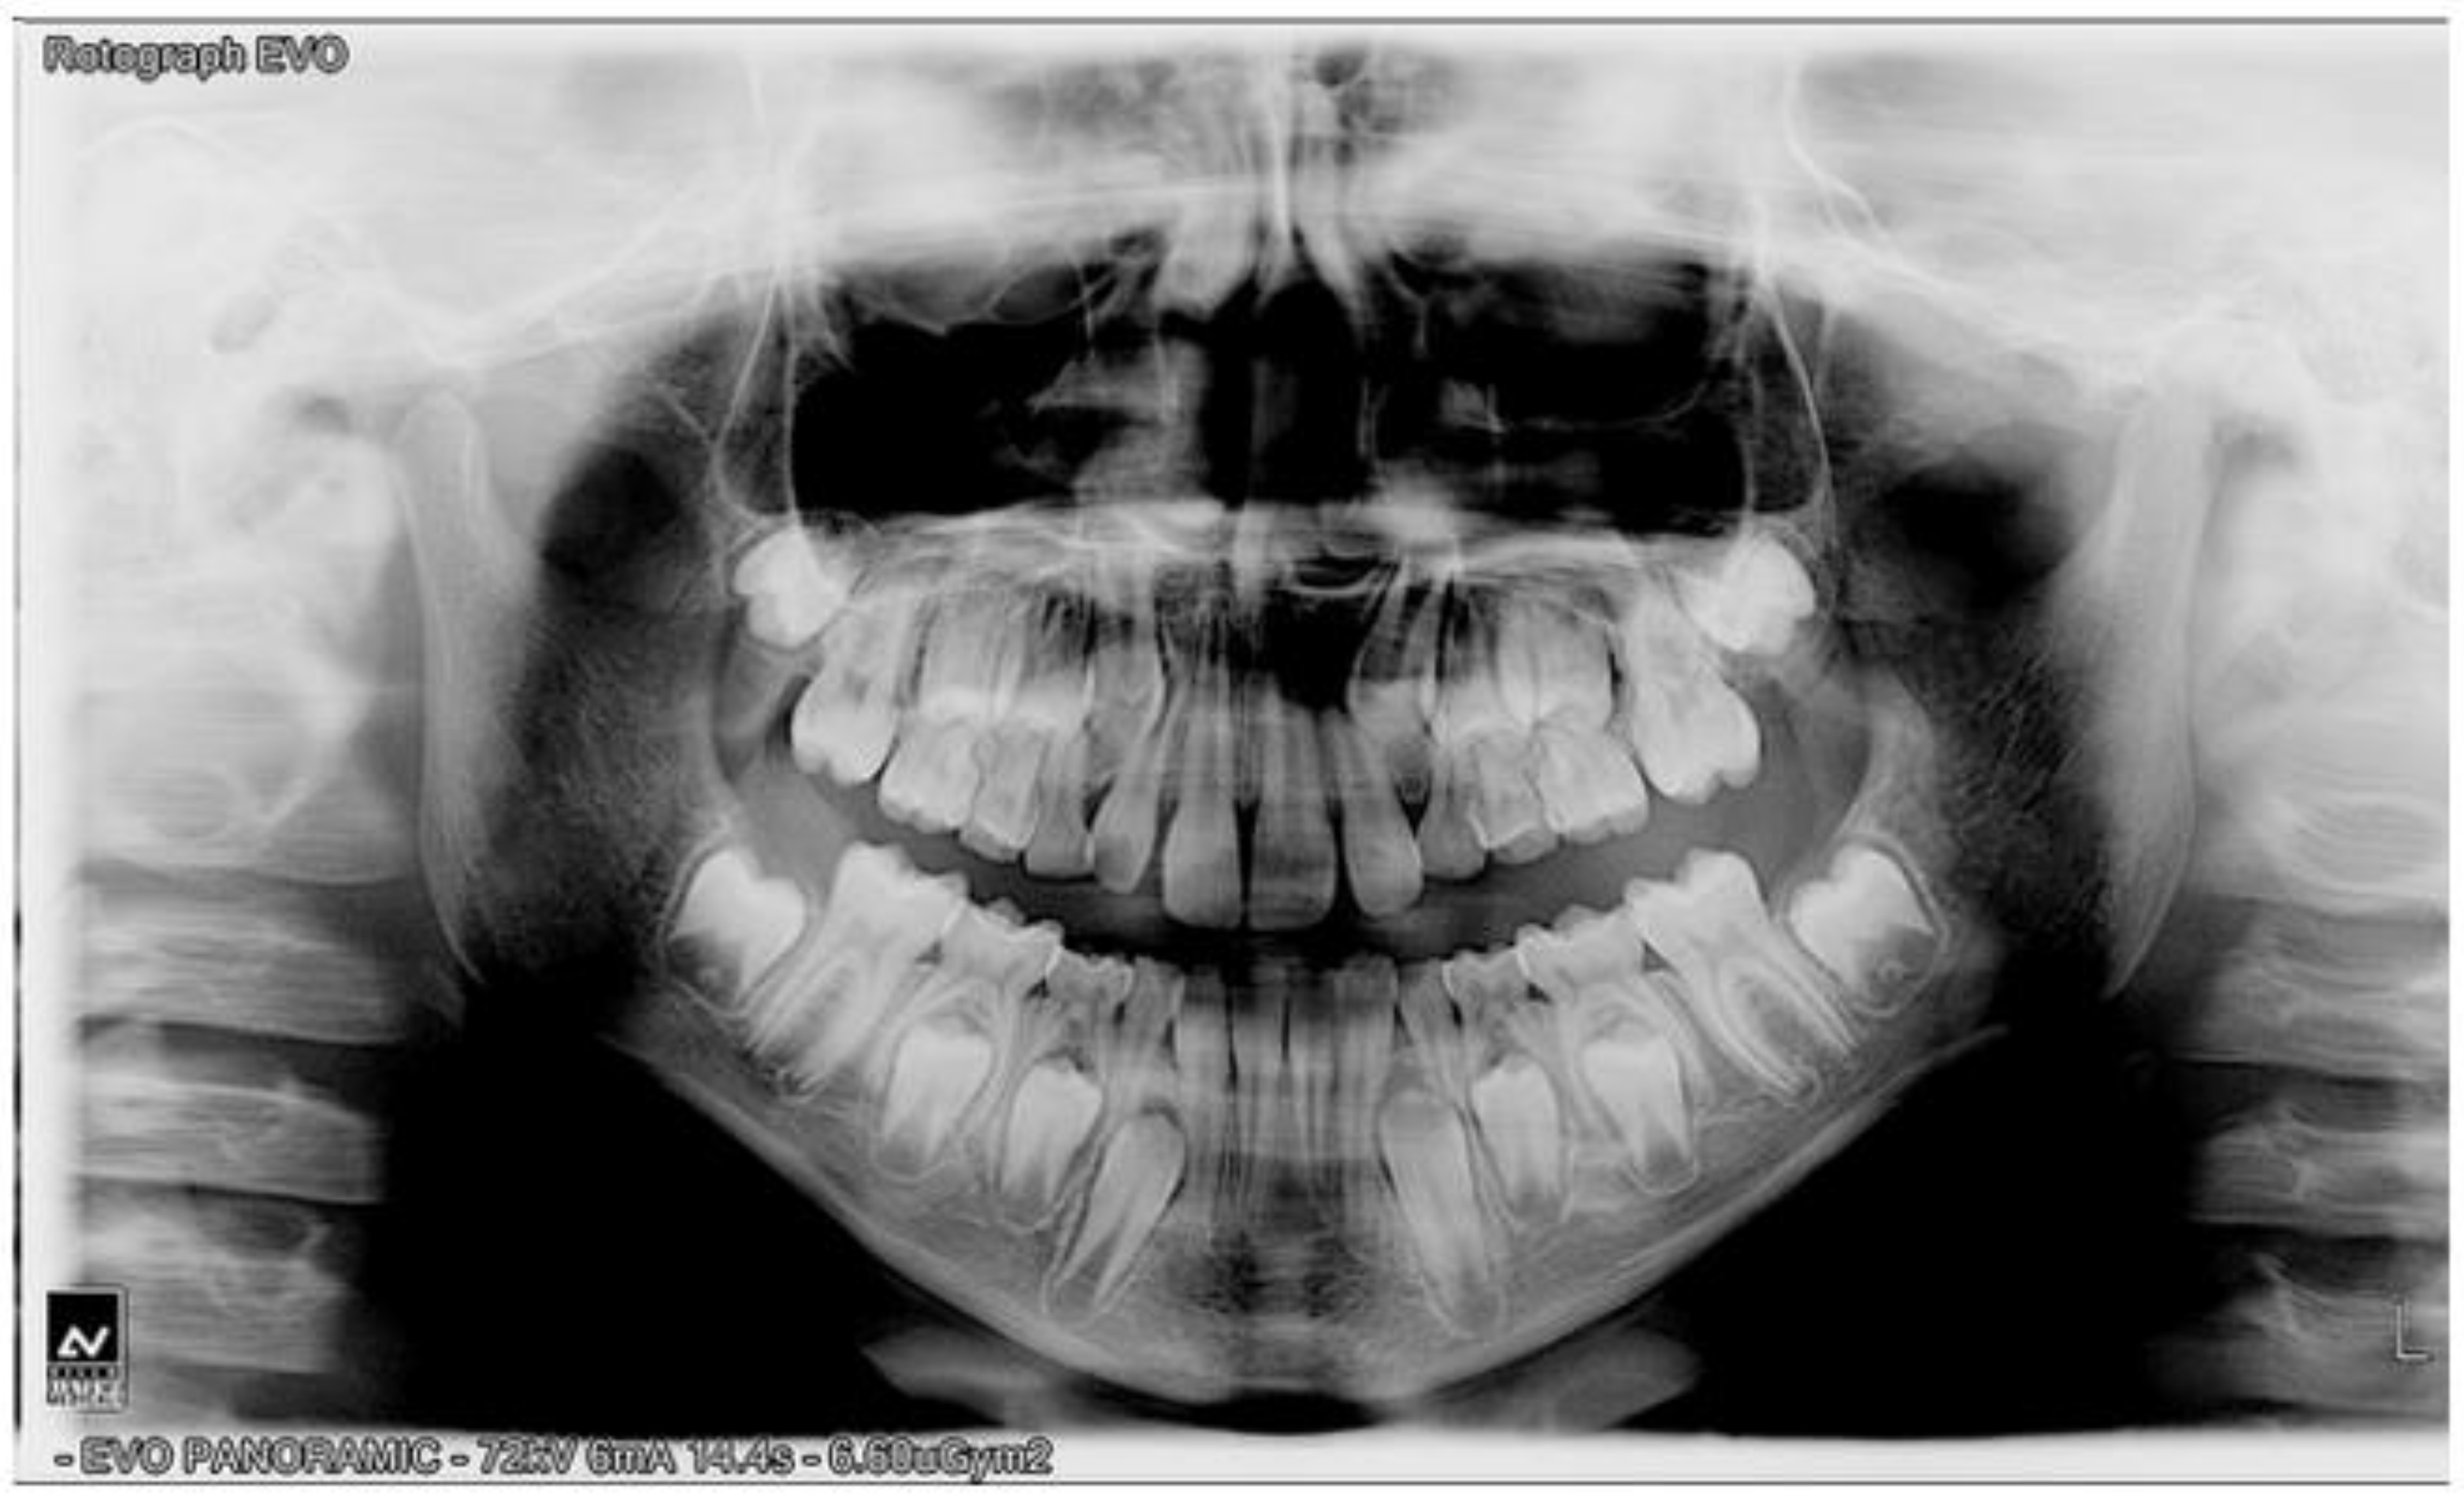

Figure 4.

Panoramic radiograph.

Cephalometric analysis revealed a skeletal class III discrepancy (ANB = −1.4^) with increased mandibular body length (Go-Gn = 70.2 mm), severe negative value of facial convexity angle (Na-Apo^ = −6.4^), hyperdivergent mandibular vertical growth pattern (MP-SN = 31.9^), and significant retro-inclination of the lower incisors (IMPA^ = 80) (Figure 3A,B). Comparing intra-oral and cephalometric data, there was a remarkable inconsistency between dental malocclusion (Class II) and skeletal sagittal discrepancy (Class III) that could be attributed to the dental compensation of the malocclusion. The panoramic radiograph revealed a normal stage of tooth eruption and an absence of inflammatory conditions (Figure 4).